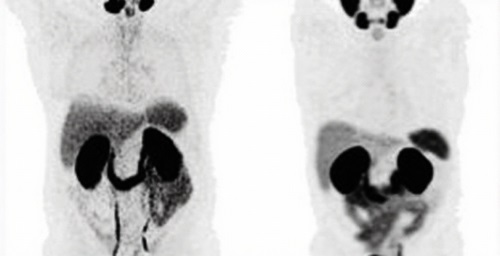

鎦-177-PSMA治療兩周年:看似輕鬆的治療,背後的挑戰與突破

醫學教室

2024-12-17